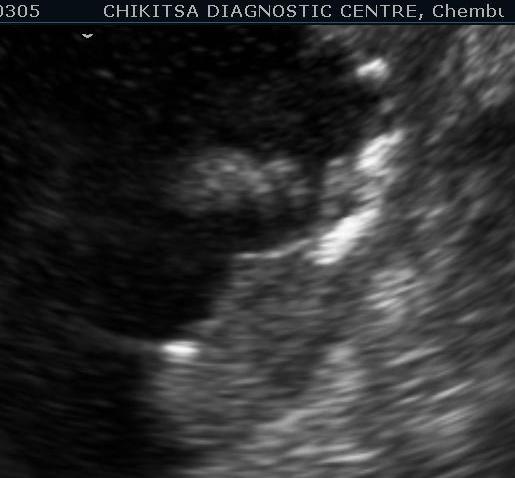

March 2012 :

5 5 cm x 5 cm size ill-defined heterogeneous area in the posterior wall of the urinary bladder which is thickened and measures upto 0.6 cm in thickness. Large solid calcific areas are noted in the thicknened portion of the wall urinary bladder. Suggestive of schistosomiasis of the urinary bladder (possibly with malignant change).

Left kidney shows hydronephrosis.